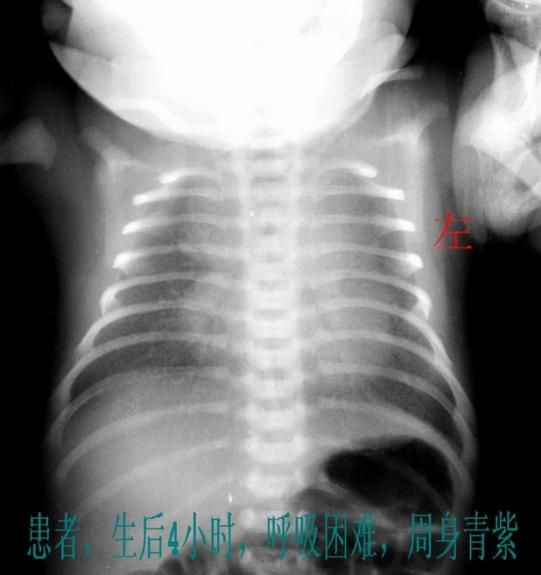

新生儿呼吸窘迫综合征亦称新生儿肺透明膜病,为肺表面活性物质缺乏诱发的一种疾病,为新生儿常见疾病,常见于新生儿32周前新生儿出现呼吸窘迫综合征后,一般表现为呼吸困难鼻翼煽动呼气性呻吟及吸气性三凹征等症状临床检查时,一般可发现其呼吸较弱,此时,可为新生儿拍摄胸部平片,以针对具体病症,做出;新生儿呼吸窘迫综合征是由肺泡表面活性物质缺乏所导致的一种疾病,以下是对该病的简要介绍一主要发病人群 早产儿尤其是小于32周的早产儿 特定生产方式的新生儿患有糖尿病的母亲还没有发动产程就进行剖宫产的小孩 出生后窒息的新生儿二临床表现 早期表现与原发疾病相关,如因严重感染。

新生儿呼吸窘迫综合征NRDS是早产儿常见的呼吸系统疾病,主要由肺泡表面活性物质缺乏导致肺泡萎陷,引发呼吸困难一核心症状新生儿呼吸窘迫综合征的典型表现为呼吸急促呼吸频率加快,伴喘息或呻吟呼吸困难鼻翼扇动吸气性凹陷皮肤青紫缺氧导致黏膜及四肢末端发绀及喂养困难因呼吸费力导致;其他相关表现患儿可能伴随反应低下肌张力减弱喂养困难等非特异性症状实验室检查可见血气分析提示低氧血症PaO#8322lt50mmHg及高碳酸血症PaCO#832250mmHg,胸片显示“白肺”或细颗粒状阴影临床意义新生儿呼吸窘迫综合征是早产儿死亡的主要原因之一,及时识别症状并启动治疗如表面活性。